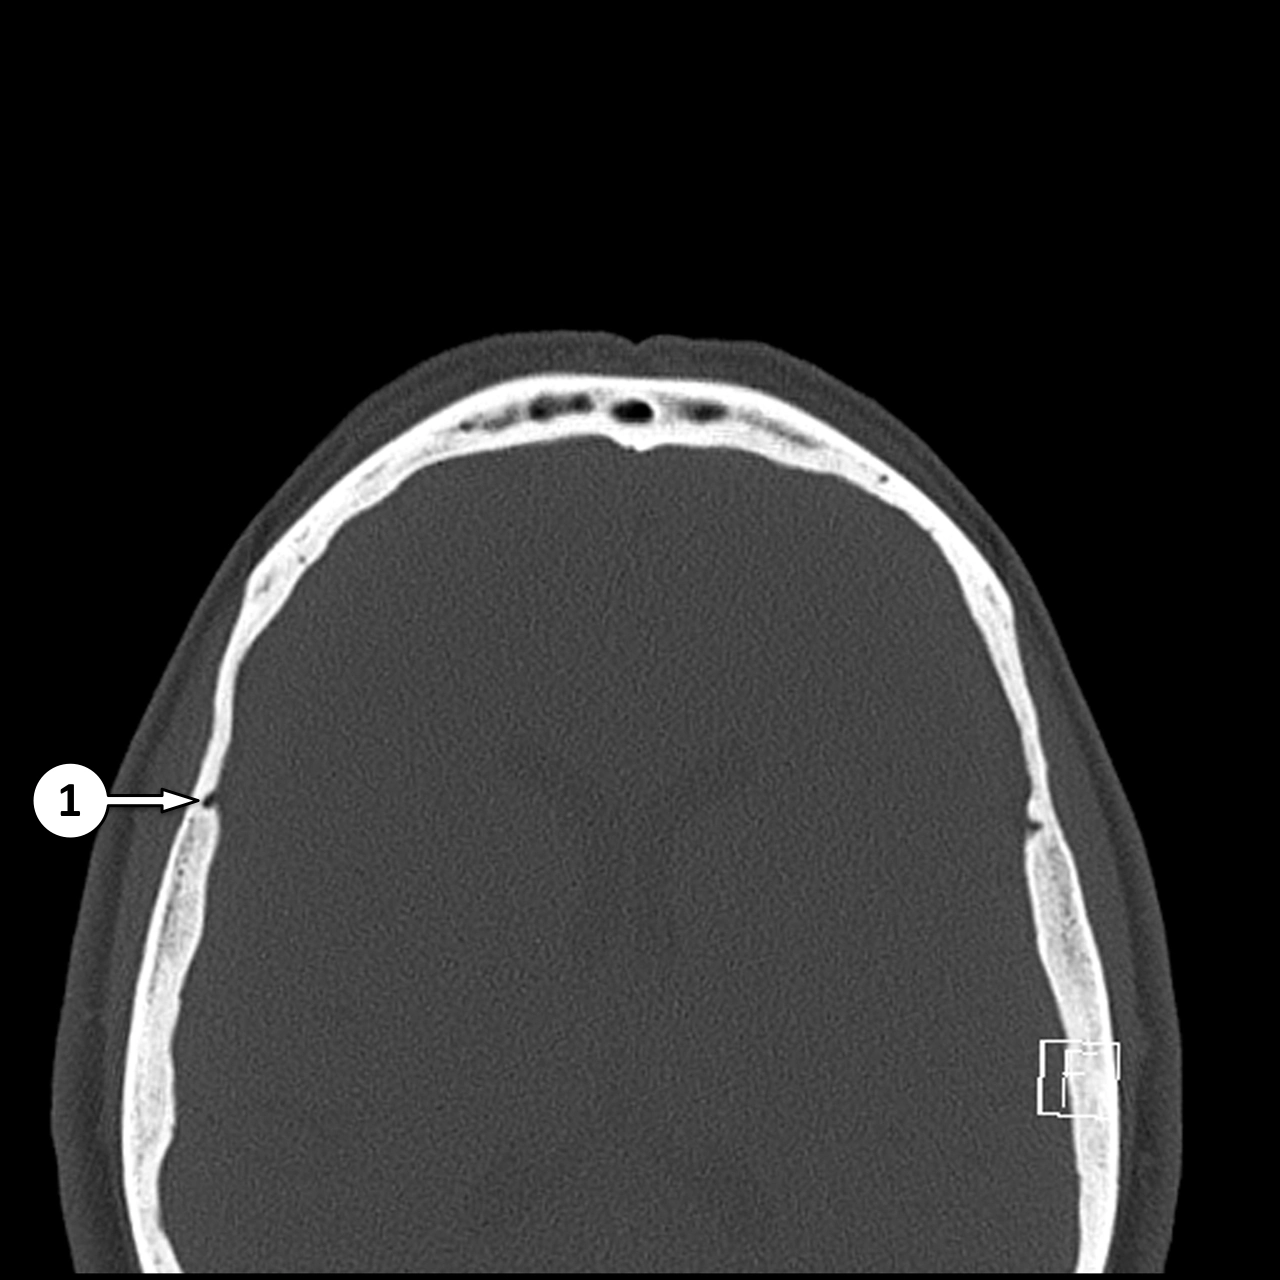

CT xương sọ